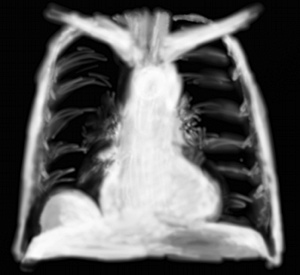

Radiologiquement l’emphysème associe une distension thoracique (thorax vertical) et une hyperclarté des deux champs pulmonaires. Les zones de grandes bulles sont encore plus claires, avec un espace totalement noir à la radiographie donnant des aspects de pneumothorax aberrants.

L’image radiographique est une hyperclarté linéaire bilatérale, mais souvent difficile à percevoir des 2 côté en même temps, en une ligne bordant le coeur. Elle forme une sorte de fausse enveloppe.

Hyperclartés en croissant, poches d’air sous les deux coupoles diaphragmatiques par issue d’air gastrique, intestinal, colique ou restant de pneumopéritoine de coelioscopie; ou parfois si l’issue d’air est énorme, grosses bulles d’air qui voilent les coupoles.